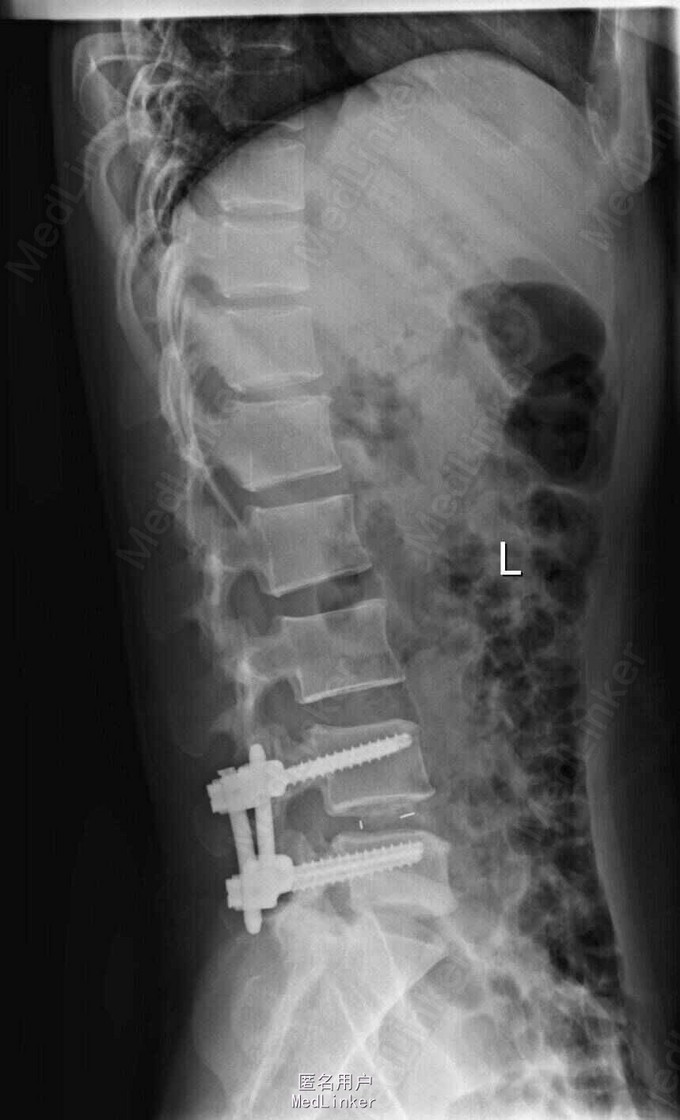

主诉:左下肢疼痛伴腰痛1月 病史:患者女性,39岁,十月前无明显原因发生腰痛,休息后缓解。未做其他治疗,1月前,出现左腿放射性疼痛,外侧及足后为主,腰部酸胀,无麻木等异常感,腰部活动障碍,不能正常行走,发病来大小便正常。在外院行ct检查后,诊断为腰椎间盘突出,未见影像片。

查体:脊柱无侧弯,腰部叩痛,活动障碍。上肢肌力感觉均正常。左下肢疼痛伴稍麻木感,肌力可,跟膝腱反射正常,直腿抬高试验:左侧55度,右侧35度,病理征未引出。 辅助检查:x线见腰椎退行性改变 MRI:L4-5,L5-S1椎间盘突出

诊断:L4-5,L5-S1椎间盘突出 治疗;患者神经压迫症状是由L4-5节段椎间盘突出所致,手术主要对L4-5节段减压,后固定。

随访:术后患者疼痛症状减轻,术后3月活动可。